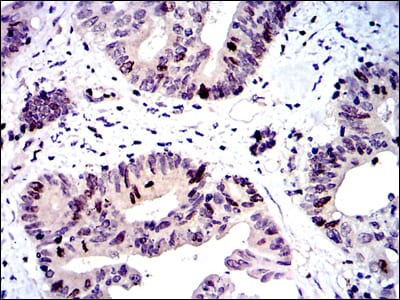

- Immunohistochemical analysis of paraffin-embedded human cervical cancer tissues using BIRC5 mouse mAb with DAB staining.

- Immunohistochemical analysis of paraffin-embedded human colon cancer tissues using BIRC5 mouse mAb with DAB staining.